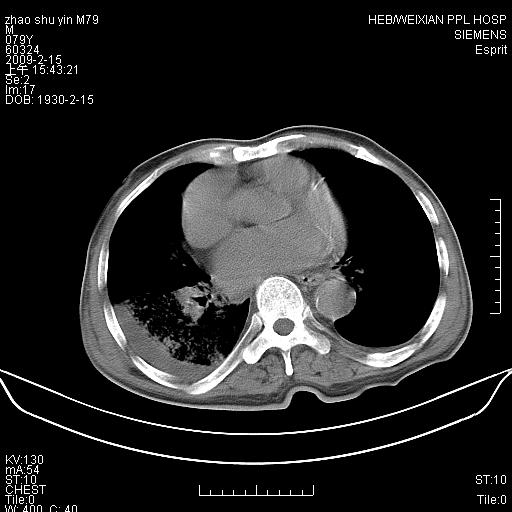

标题: CT18303:M79Y,右下肺病变

主因高热、寒战4天,伴有咳嗽,腹痛。

1。右下肺磨玻璃及蜂窝影考虑炎症 建议抗炎治疗后复查

2。右侧胸膜增厚 、右侧包裹性积液

3。心影增大 ,左心房增大为甚

4。右下肺门饱满(肿大淋巴结)